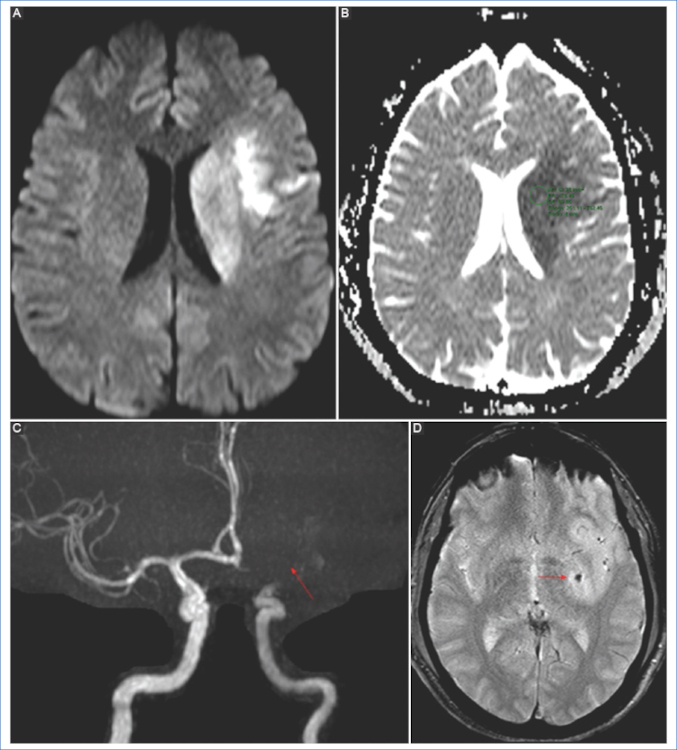

Algunos autores sugieren que un valor bajo del coeficiente de ADC menor a 550 × 10−6 mm2 es un predictor independiente de transformación hemorrágica luego de la trombólisis 9,10 (Fig. 2).

En la isquemia de origen cardioembólico se observan lesiones en múltiples territorios vasculares de manera bilateral, supra e infratentorial, o bien una lesión única distal cortical/subcortical5 (Fig. 4).

Secuencias de susceptibilidad magnética (GRE/SWI)

En la fase aguda, tanto la TC como la RM usando secuencias de susceptibilidad magnética nos permitirán la detección de hemorragias; aunque la RM es más sensible para la detección de hemorragias petequiales (microhemorragias), de hematomas o microsangrados previos, y en la detección de trombo intraluminal en vaso de mediano calibre. Puede observarse en la RM el equivalente al signo de la cuerda hiperdensa en las secuencias de susceptibilidad, signo que tiene una alta especificidad para detectar el sitio de la oclusión. La visualización del trombo en esta secuencia se relaciona con la presencia de un trombo rojo (desoxihemoglobina), asociada por lo general a etiología cardioembólica2,5 (Fig. 7).